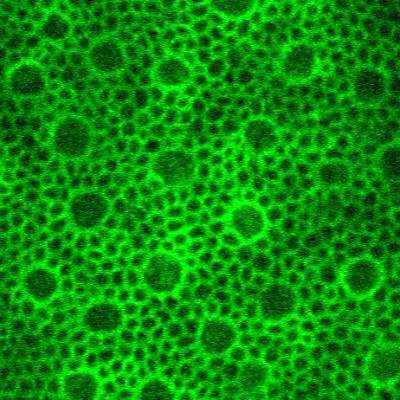

Multimodal image of retinal pigment epithelial cells.

Multimodal image of retinal pigment epithelial cells. Image generated using a combination of four adaptive optics imaging modalities (magenta = summation of adaptive optics optical coherence tomography, adaptive optics infrared autofluorescence, and darkfield; green = late phase adaptive optics indocyanine green image). Individual cells labeled by indocyanine green are contained within cell outlines visualized using complementary techniques.